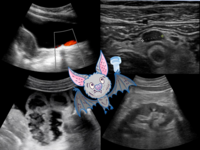

Sonographie ist als diagnostisches Instrument aus der Notfallmedizin nicht mehr wegzudenken. Non-invasiv, rund um die Uhr verfügbar und kostengünstig lassen sich mit ihrer Hilfe zeitkritische Diagnosen stellen – oder ausschließen. Auch notfallmäßige therapeutische Interventionen wie die Anlage von Drainagen oder Gefäßzugängen können sonographiegestützt schnell und sicher erfolgen. Allerdings setzt dies ein erhebliches Maß an technischem Know-How, praktischem Geschick und klinischer Erfahrung voraus. Um im komplexen Setting eines klinischen Notfalls belastbare sonographische Diagnosen stellen und die Entscheidung für oder gegen therapeutische Maßnahmen darauf stützen zu können, müssen die sonographischen Untersuchungsabläufe von Thorax, Abdomen, Retroperitoneum und Gefäßen daher systematisch erlernt und eingeübt werden.

Der Leitgedanke der Basisausbildung Notfallsonographie ist die symptomorientierte Strukturierung und Priorisierung der sonographischen Untersuchung im Notfallsetting. Damit ist dieses Format besonders für die Vorbereitung auf Tätigkeiten in allen akutmedizinischen Bereichen (z. B. Notaufnahme, Intensivstation, prähospitale Notfallmedizin) geeignet.